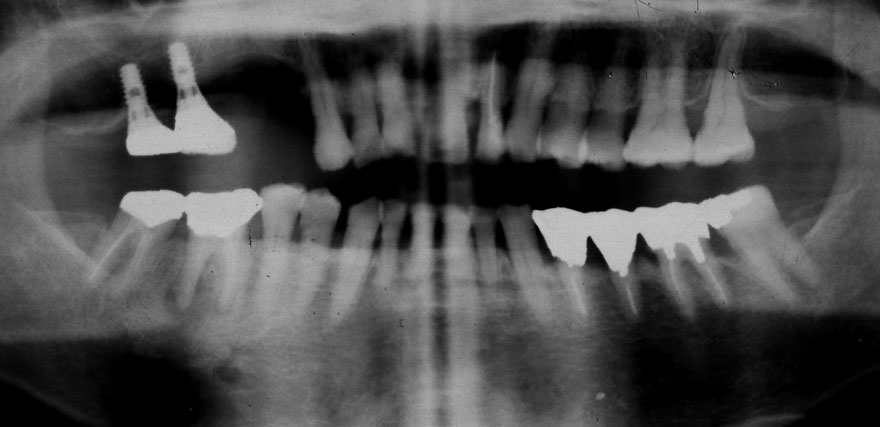

初診時 41歳 男性 平均歯槽骨喪失量:4.11mm

30年後 71歳

平均歯槽骨喪失量:3.70mm

30年間再生量:+0.41mm

年間再生速度:+0.014mm

(ケア頻度:1.27ヵ月ごと)